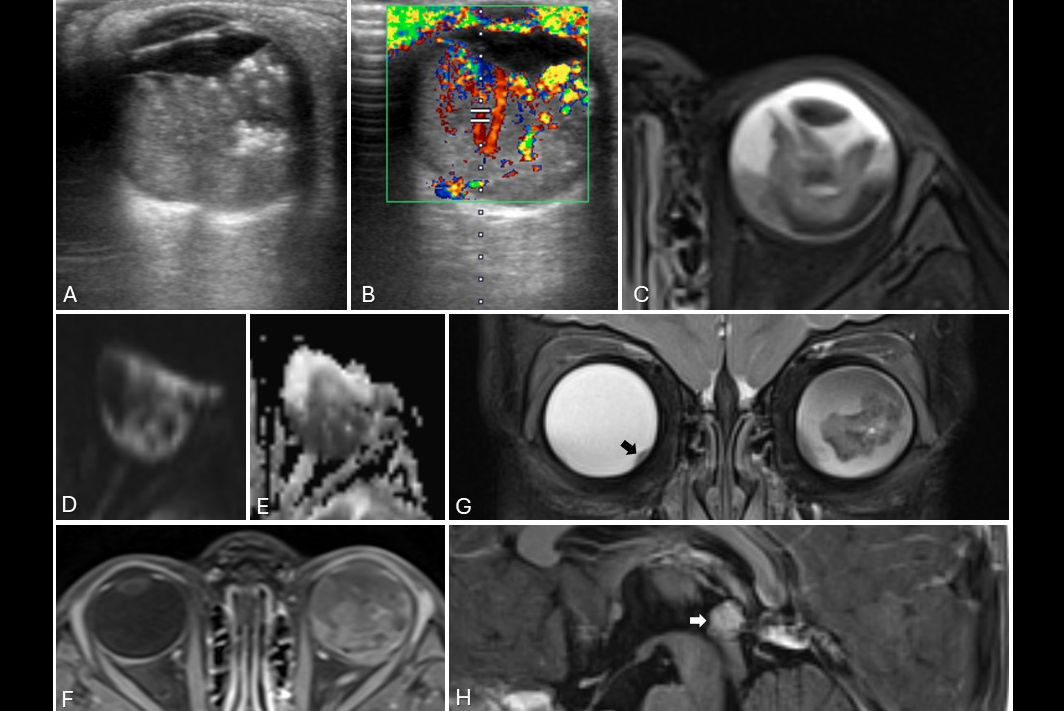

The graph shows the analysis of the weekly workload at Tsapaki's institution of the CT scanner as a function of hours and days in the week. The bar below the graph defines the colors related to the time periods of the usage. Starting from purple on the left and ending with red on the right, the color bars show the following: the actual study, the preparation time, time gap of less than 10 minutes, time gap of less than 20 minutes, time gap of less than 30 minutes, and, finally, time gap of more than 30 minutes. All images courtesy of Virginia Tsapaki, PhD.